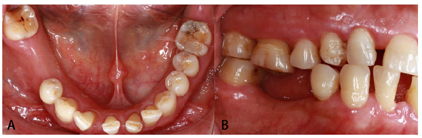

口内检查:45、46牙缺失,缺牙间隙近远中向18 mm,颊舌向9 mm,

龈距6~7 mm,对

牙略伸长,邻牙无倾斜;前牙散在间隙;张口度正常,颞下颌关节无弹响、无疼痛;缺牙区角化龈充足(图1)。

面照;B:颊面照